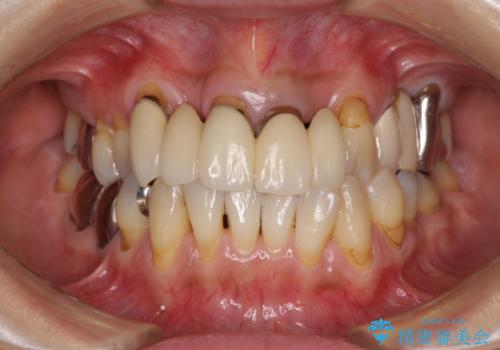

- ブリッジと歯肉の隙間にものが挟まったり空気が抜けたり、歯肉ラインの黒い縁が目立ってしまったりと、前歯のブリッジの作り直しを希望して来院された患者様です。

自然な仕上がりとするため、金属を使用しないオールセラミックブリッジにより補綴治療を行うこととしました。

露出していた歯根や金属の縁が見えてしまい、なかなか口を開けて笑うことができなかったのですが、歯肉の位置に縁を合わせることで自然な仕上がりとなりました。

ブリッジの隙間にものが詰まったり、空気が抜けたりすることも無くなり、話しやすさも改善することができました。